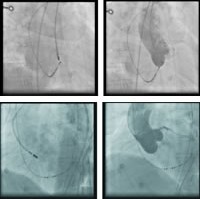

图7 消融靶点位置X线影像图(左前斜位及右前斜位)

图8 无冠窦内消融终止心动过速

经电解剖标测和CT成像(CARTO-merge,图6)、主动脉根部造影(图7)证实,最早激动点位于无冠窦,在此处予以盐水灌注(35W,45℃)17ml/min,消融房速即刻终止(图8),猝发刺激及静脉滴注异丙肾上腺素未诱发任何心动过速。